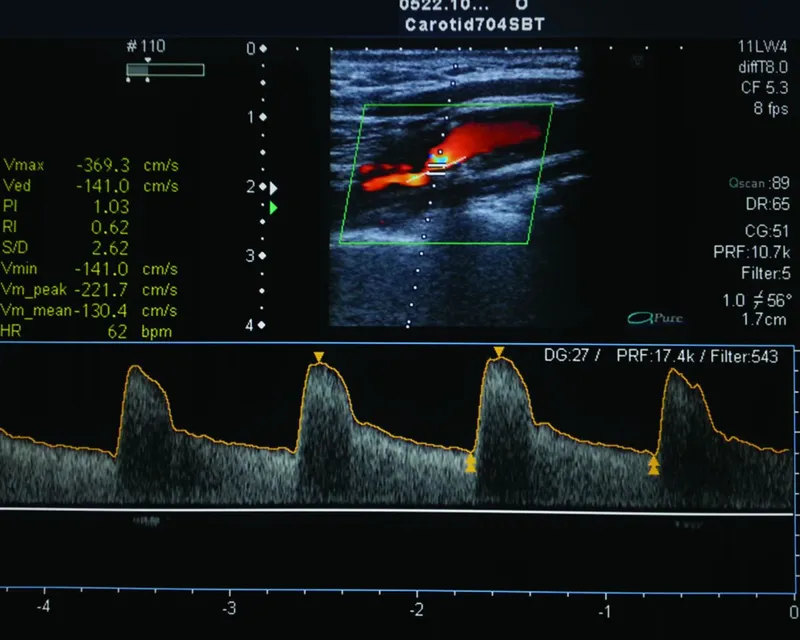

- Initial Test: Carotid Duplex Ultrasound. Non-invasive, uses ↑ peak systolic velocity (PSV) and end-diastolic velocity (EDV) to estimate stenosis severity.